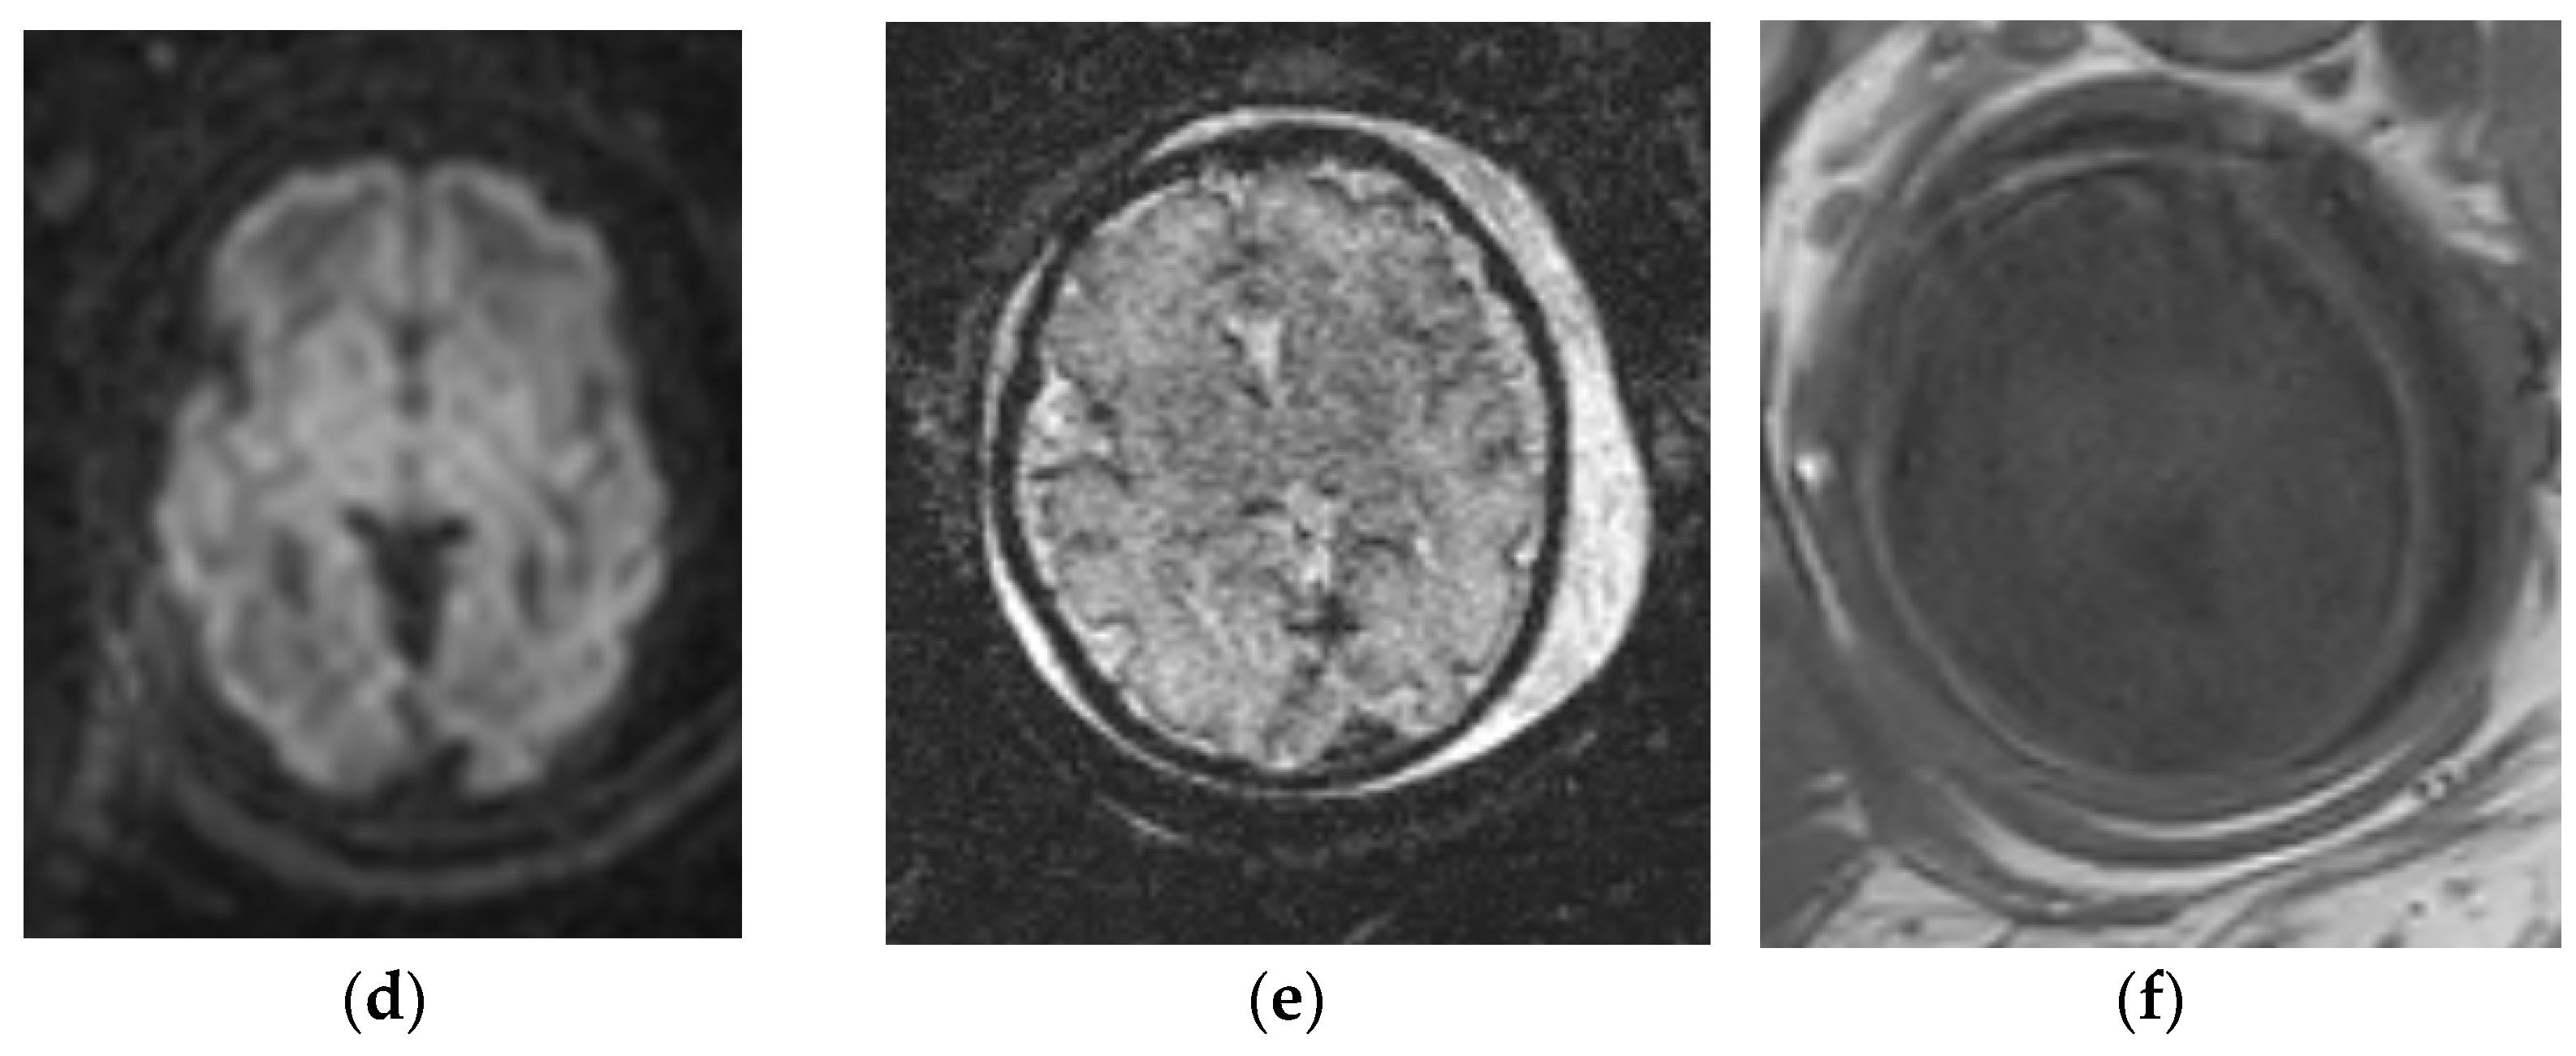

4.1. Holoprosencephaly Spectrum

4.2. Corpus Callosum Anomalies

4.3. Hypoplastic Optic Nerves vs. Isolated Septal Deficiency

- Nagaraj, U.D.; Calvo-Garcia, M.A.; Kline-Fath, B.M. Abnormalities Associated With the Cavum Septi Pellucidi on Fetal MRI: What Radiologists Need to Know. AJR Am. J. Roentgenol. 2018, 210, 989–997. [Google Scholar] [CrossRef]

- Winter, T.C.; Kennedy, A.M.; Woodward, P.J. Holoprosencephaly: A survey of the entity, with embryology and fetal imaging. Radiographics 2015, 35, 275–290. [Google Scholar] [CrossRef]

- Riddle, A.; Nagaraj, U.; Hopkin, R.J.; Kline-Fath, B.; Venkatesan, C. Fetal Magnetic Resonance Imaging (MRI) in Holoprosencephaly and Associations With Clinical Outcome: Implications for Fetal Counseling. J. Child Neurol. 2021, 36, 357–364. [Google Scholar] [CrossRef]

- Palmer, E.E.; Mowat, D. Agenesis of the corpus callosum: A clinical approach to diagnosis. Am. J. Med. Genet. Part C Semin. Med. Genet. 2014, 166, 184–197. [Google Scholar] [CrossRef]

- Tang, P.H.; Bartha, A.I.; Norton, M.E.; Barkovich, A.J.; Sherr, E.H.; Glenn, O.A. Agenesis of the corpus callosum: An MR imaging analysis of associated abnormalities in the fetus. Am. J. Neuroradiol. 2009, 30, 257–263. [Google Scholar] [CrossRef] [PubMed] [Green Version]